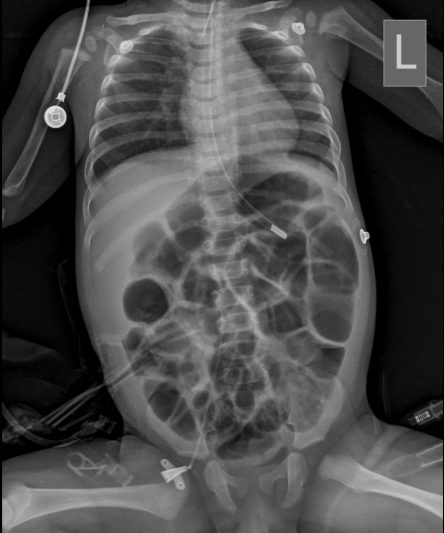

Microskan with Ultra high frequency can take the Lateral Lumbar Spine image of a 90 kg Patient with the correct image receptor